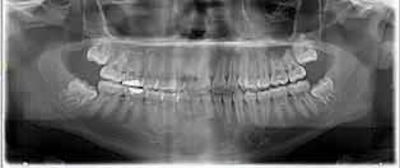

A clinical exam found that the boy had severe right periorbital and midface edema, as well as mild emphysema of the right upper eyelid. An eye exam showed 20/20 vision with no optic nerve problems, mild restriction to adduction, and slightly elevated intraocular pressure. Intraorally, tooth #3 had a large restoration with adjacent fluctuant vestibular swelling but no active drainage.

In addition, a CT scan taken at the outside hospital was reviewed by medical center clinicians. They identified a subperiosteal abscess at the right lateral orbit. The right canine space abscess came from the buccal roots of tooth #3. Also, the scan showed that fluid collected at the right canine space superiorly and posteriorly to the right lateral orbit, and right maxillary sinusitis was present.